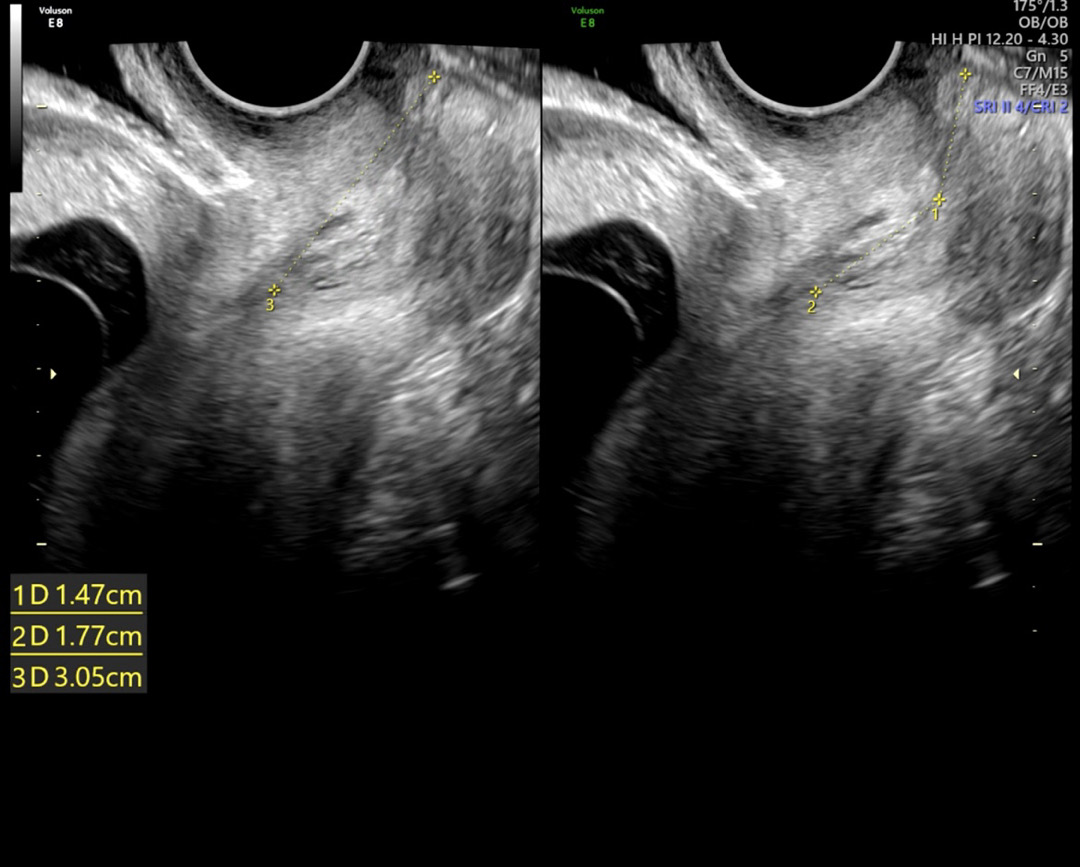

경부길이

12주5일차 입니다 경부길이가 몇센티 인건가요? ㅜㅜ 1D 2D 3D 중에 뭐를 봐야할까요.. 선생님이 좀 짧다고 3주 후에 오면 다시 보자고 하시고 그냥 무거운거 들지 말고 배에 힘주지 말라고만 하시는데 다른 글들 보니까 경부길이 짧으면 무조건 누워 있으라는데.. 의사선생님께서는 막 엄청 조심하세요 이렇지 않아서 어떻게 해야할지 모르겠어요 그래도 큰 병원에 계신 분이긴 한대.. 임신이 처음이라 걱정이네요..